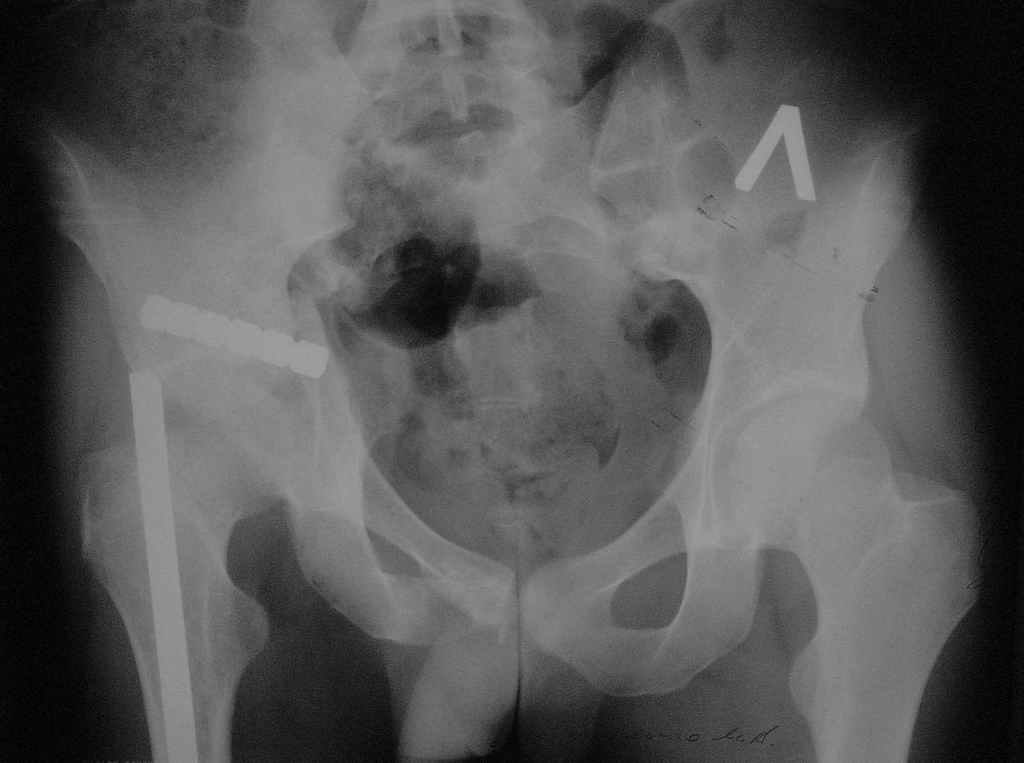

Пример лечения стабильной деформации с вертикальным смещением половины таза.

отеотомия передних и задних отделов, дистракция аппаратом

|